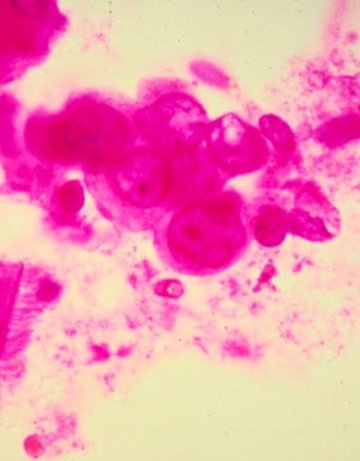

Изследователи от Бирмингамския университет създадоха модифицирана форма на екстази, 100 пъти по-ефикасна при

успешното атакуване на раковите клетки, съобщи АФП.

Новият препарат, наречен MDMA, ще разчисти пътя към терапевтичната му употреба при трудната борба с раковите

заболявания. Британските учени се основават на изследванията, проведени преди 6 години, които са установили, че половината от раковите клетки в кръвта реагират на психотропните вещества и спират развитието им.

По-късно в сътрудничество с австралийски колеги, британският екип е разработил много по-ефикасна разновидност на "дрогата от дискотеките", която действа срещу раковите клетки при минимални дози.

Със стократно по-високата си ефективност, тези препарати ще бъдат използвани в обозримо бъдеще за третирането на левкeмии, лимфоми и миеломи.